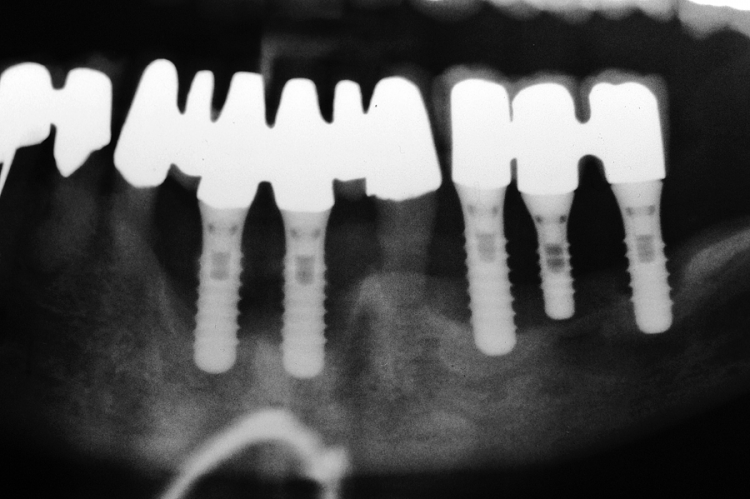

Между тем, в практике существует масса примеров, когда это правило не соблюдается, и расстояние от имплантата до соседнего зуба, либо от импланта до импланта существенно меньше назначенного Гамбореном Зукелливичем Урбаняном:

Не суть. Важно понять, что крутящий момент при установке имплантата — это решающий фактор, от которого, в дальнейшем будет зависеть как риск осложнений, так и состояние костной ткани вокруг имплантата. Или вокруг нескольких имплантатов:

А сейчас давайте рассмотрим состояние кости между имплантами с учётом того, что мы знаем о силе и давлении.

Получается так, что между двумя имплантами остаётся сильно сжатый участок кости. Который, в случае I или II биотипа и так кровоснабжается не очень, а тут еще и сдавливается вхлам. Его кровоснабжение на нуле, а мы-то с вами знаем, что всё, что не кровоснабжается в нашем организме, отваливается нафиг. Нет питания — нет регенерации. К сожалению:

Чем меньше этот участок по размерам, тем больше он сдавливается, тем хуже его кровоснабжение.

Итак, как вы видите, существующее правило вполне понятно. Справедливо. И объяснимо, с точки зрения физики и биологии. И всё, вроде бы, классно, если просто хреначить имплантаты в челюстную кость, не думая о последующем протезировании.